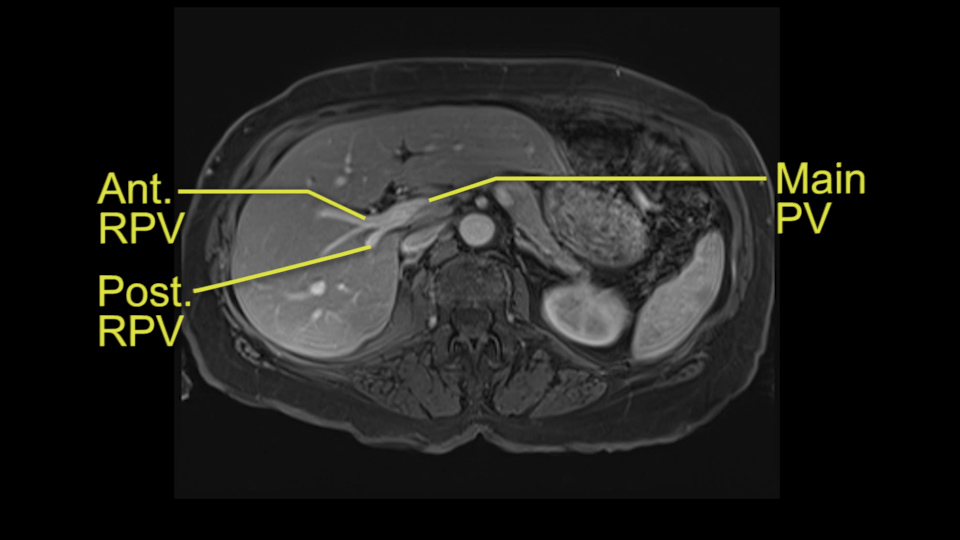

So we’re going through the liver segments now. Here we’ve got the inflow; here’s the main portal vein, right anterior sectoral portal vein, right posterior sectoral portal vein there. Here’s the main here going to the left lobe first of all. So that’s 3 and 2 there, they look clear, and there’s a good size of the left lobe with a good girth. So 3 and 2 look clear. There are usually more feedback branches from the left portal vein to segment 4b but that also looks relatively clear. There’s a little more disease over on the right side there. So that would be...right hepatic vein here...that’s Segment 7. So we’ve got disease in 7, 5, probably in 6 on the right side; at least 3 lesions. That’s the distribution of the lesions.![[Ant. RPV] [Main PV] [Post. RPV]](jpg/preop_as_p5.jpg)

So look at the MR from two points of view, firstly distribution of the lesions, secondly what kind of parenchyma would need to be resected to remove that disease and what kind of operation would we plan. And again so what we’re planning here would probably be a right hepatectomy. We know that there is plenty of disease-free left lobe. Segment 4 looks nice and clear. So a transection line coming down to about that kind of area would clear all of the disease. So that’s the kind of preoperative planning that we’d need to do.